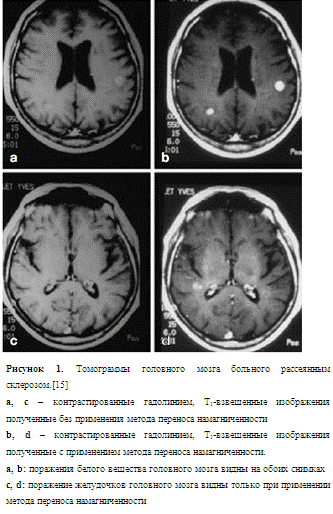

Применение того или иного принципа контрастирования, обуславливается диагностической задачей стоящей перед исследователем. Одной из наиболее актуальных задач на данный момент, являются: обнаружение ранних стадий развития рассеянного склероза. Клинические исследования показали что методика MTI оказывается более чувствительной к изменениям белого вещества мозга у больных рассеянным склерозом, чем остальные методики МРТ, используемые для диагностики данного заболевания.[6]

Метод переноса намагниченности оказался эффективным для визуализации очагов рассеянного склероза.[7] Применяется использование этого метода в сочетании с искусственным контрастированием. Применяя стандартные методы и перенос намагниченности, Д. В. Пати и Г.Воробейчик (1999) выявили корреляцию данных МРТ с патофизиологическими изменениями в очагах в динамике лечения больных рассеянным склерозом.

Контраст изображений, полученных с помощью методов MTI, отражает соотношение и биофизическое взаимодействие между свободной водой и водой, связанной с биомолекулами. Использование MTI повышает чувствительность MPT-методов при патологических процессах, связанных с деструкцией клеточных мембран и изменением характера связи воды с белками. Важным преимуществом MTI является возможность объективной количественной оценки результатов с помощью величины, называемой отношением переноса намагниченности.[8]